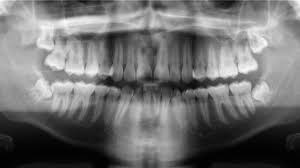

Korszerűen felszerelt rendelőjében naponta 18-26 pácienst is “ellátott”, csakhogy idővel egyre több panasz érkezett ellene: szükségtelenül húzott ki fogakat, ép fogak idegeit ölte el vagy túl kicsi koronát tett fel.

Mint kiderült, hamis papírokkal nyitott rendelőt a kisvárosban és alaposan túlszámlázta a helyieknek nyújtott szolgáltatásait, direkt rosszul dolgozott, hogy többször kelljen hozzá járniuk a pácienseknek. Eközben a város mellett egy fényűző házban élt és majdnem egymillió eurós adósságot halmozott fel.

A férfit a francia társadalombiztosítás kárára elkövetett csalással, valamint azzal vádolták, hogy “erőszakkal” csonkította meg betegeit és okozott nekik maradandó károsodást.

A francia eljárásban a mintegy száz panaszos közül az ügyészség 53 esetben ismerte el a csonkítást, 20 másik esetben előre megfontolt erőszakkal vádolta a gyanúsítottat, három esetben pedig felmentést kért.